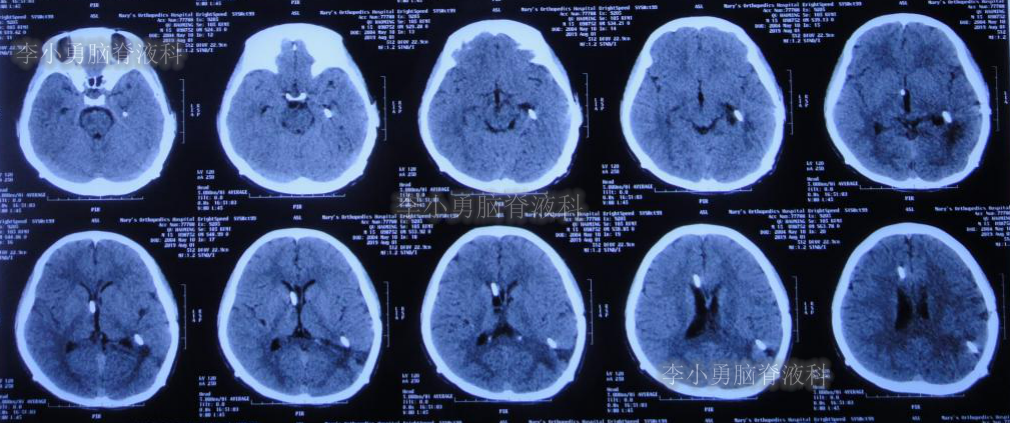

双侧脑室外引流5天后即2019年3月31日,脑脊液颜色由血性明显变淡,意识转清,肢体活动良好,给予复查头颅CT(图-3):脑室不大,残留少许积血。

图-3:2019年3月31日头颅CT:残留少许积血

双侧脑室外引流6天即2019年4月1日,给予常规拔除双侧脑室外引流管。但当晚再次出现剧烈头痛、烦躁及恶心,复查头颅CT(片子遗失)示脑室内再次出血,给予“对症处理”。

次日即2019年4月2日给予行腰椎穿刺术,引流出血性脑脊液;但腰椎穿刺术刚结束突然晕厥,再次复查头颅CT(图-4):脑室内出血量较前明显增多,四脑室及中央导水管铸形。

图-4:2019年4月2日头颅CT:脑室内积血明显增多